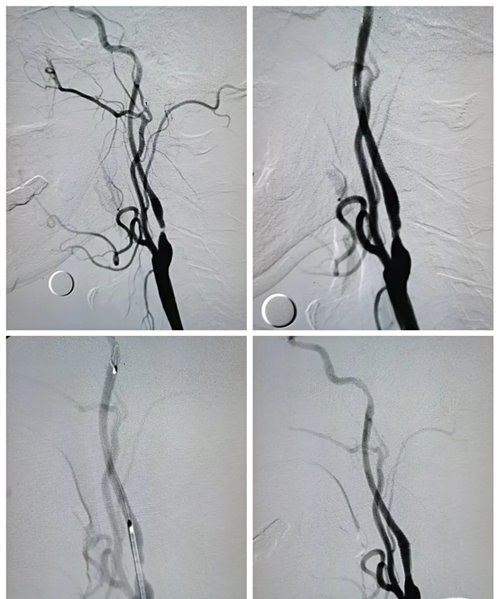

(二)介入治疗革新

颈动脉支架置入术(CAS)适用于高龄或手术风险患者,药物涂层支架可使再狭窄率从20%降至8%。血流导向装置可改变局部血流动力学,减少斑块冲击力。对于软斑块,激光消融技术可精准去除脂质核心。